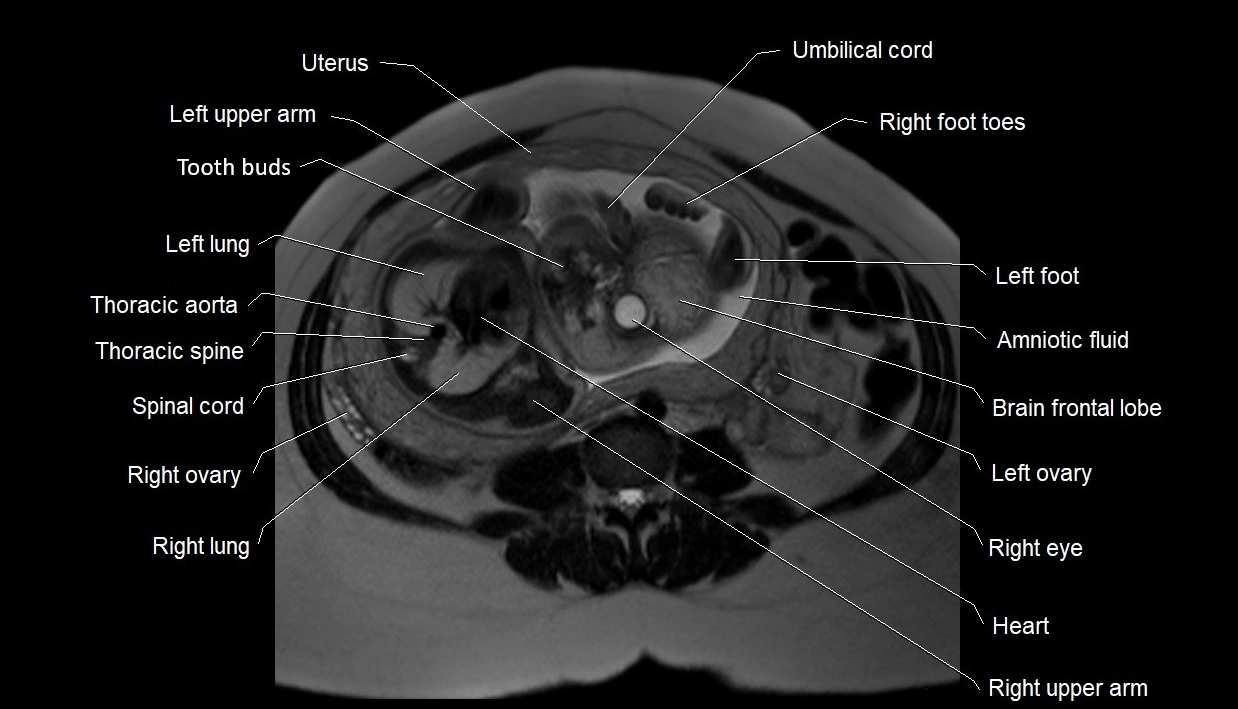

MRI Appearance

T2 HASTE (T2 GRE):

• Amniotic fluid shows very bright hyperintense signal

• Provides natural contrast against fetus and placenta

• Small particles (vernix) may appear as scattered hypointense foci within bright fluid